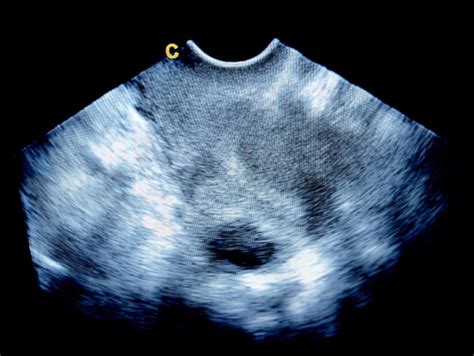

Čeprav ultrazvok predstavlja glavno diagnostično orodje za odkrivanje miomov, je pomembno vedeti, da so meritve lahko neposredne in nekoliko popačene. V redkih primerih se lahko prikažejo večji miomi, kot so v resnici, ali pa se manjši miomi ne zaznajo. Zato je pomembno zaupati oceni zdravnika in upoštevati vse dejavnike, ki vplivajo na plodnost in nosečnost.